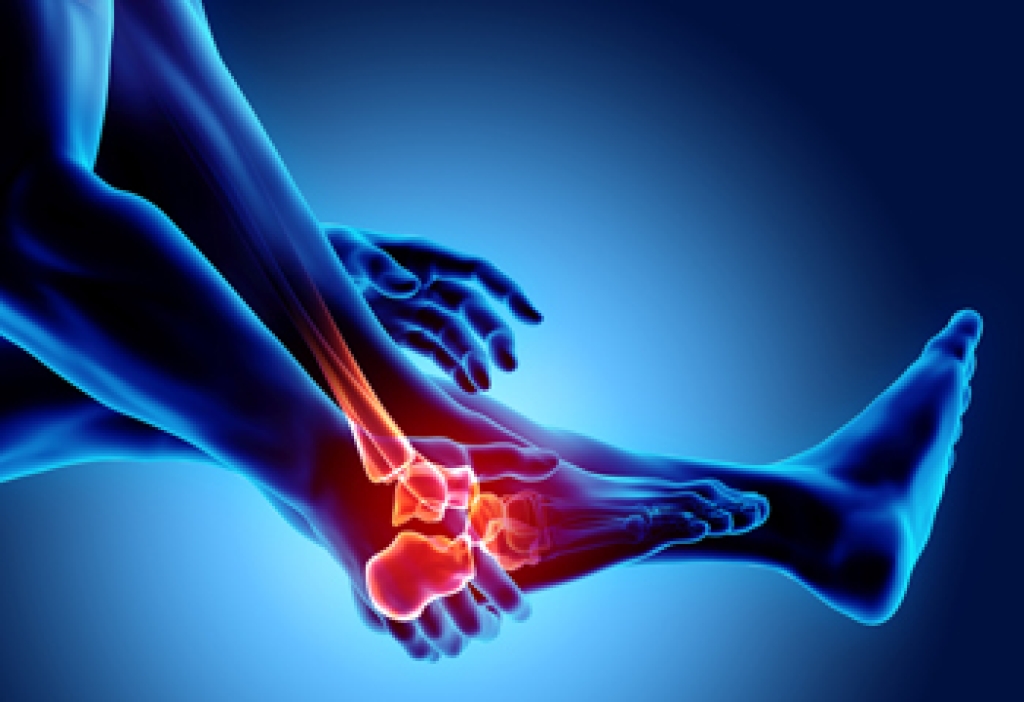

Arthritis in the feet is a condition that can bring a range of discomforts and unique sensations. It often manifests as pain and stiffness in the joints, making every step a potential challenge. Individuals with foot arthritis may experience a deep, aching pain that worsens with movement. This discomfort can be present in various areas of the foot, including the toes, the midfoot, or the ankle. One common sensation associated with foot arthritis is a feeling of stiffness or inflexibility. It can be particularly pronounced in the morning or after periods of inactivity. As arthritis progresses, swelling and warmth may accompany the pain, making the affected foot feel tender to the touch. In more advanced cases, individuals may notice a grinding or popping sensation in the affected joints, indicating the wear and tear of the cartilage. Understanding what arthritis in the feet feels like is essential for timely diagnosis and effective management. If you have any of the above symptoms which may indicate arthritis in the feet, it is suggested that you schedule an appointment with a podiatrist who can guide you toward relief methods.

- Swelling

- Pain

- Stiffness

Arthritic symptoms range in severity, and they may come and go. Some symptoms stay the same for several years but could potentially get worse with time. Severe cases of arthritis can prevent its sufferers from performing daily activities and make walking difficult.